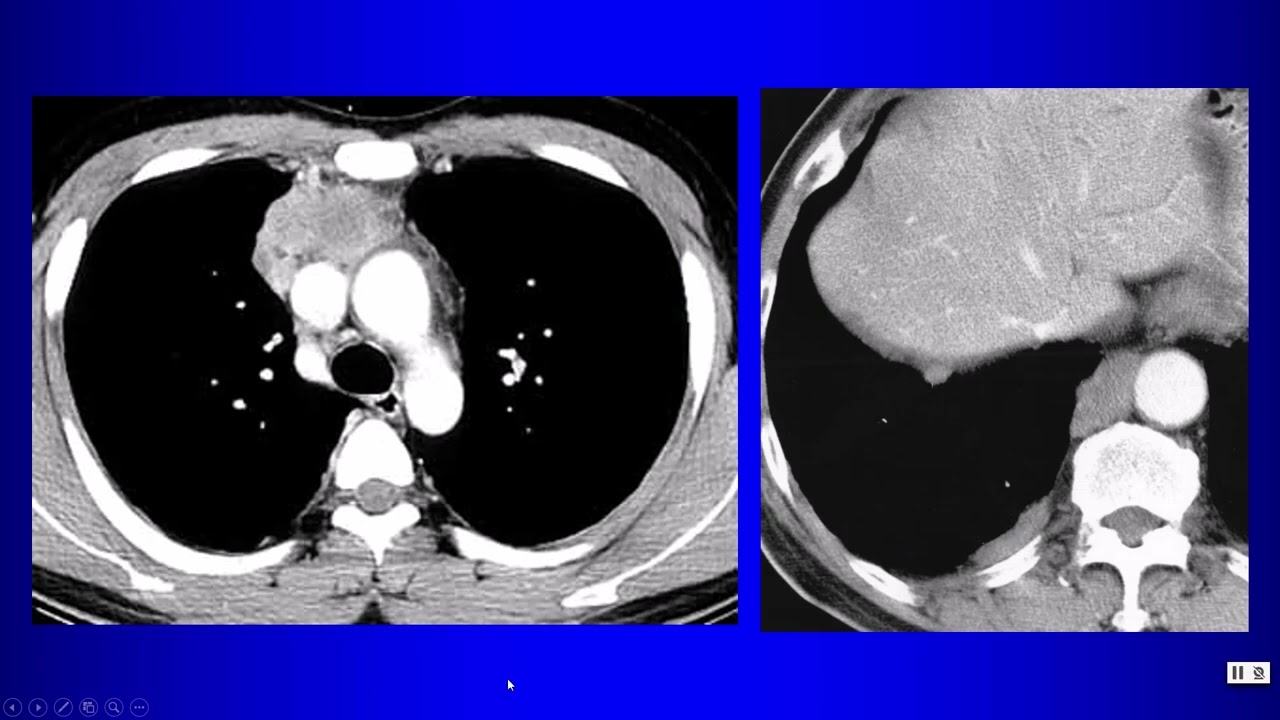

Case Discussion : Anterior Mediastinal mass

Try to answer

where is the mass located

Try to analyze the available radiological signs

see the next step of investigation